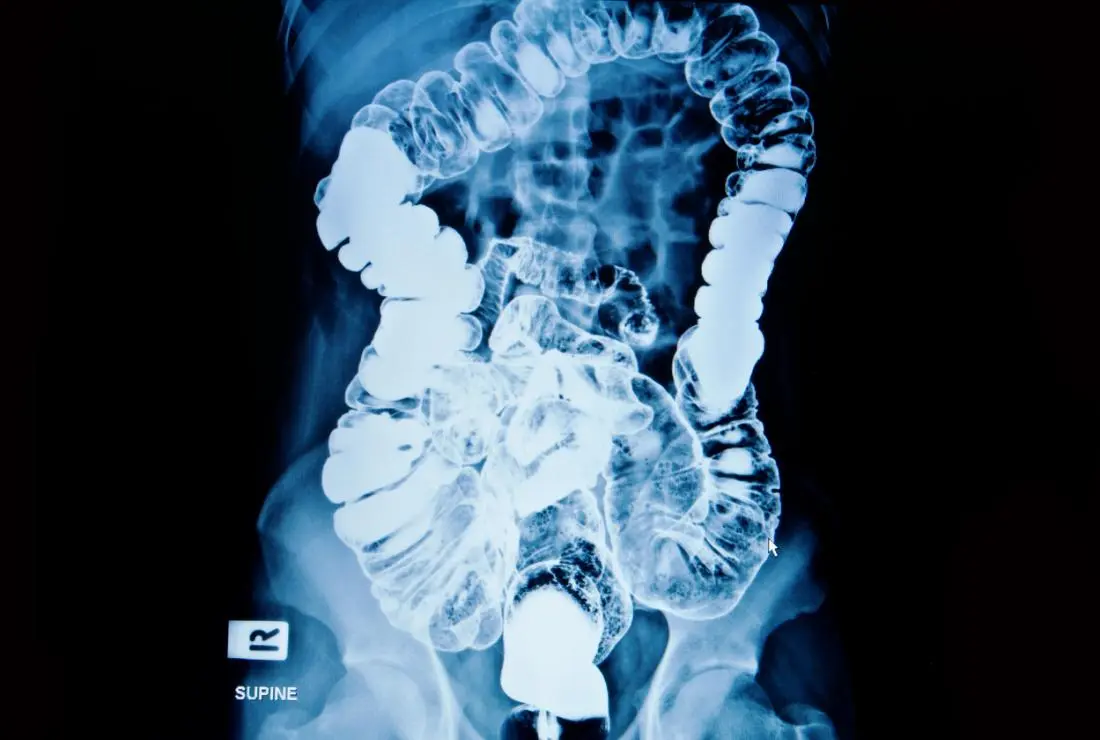

We provide quick and accurate Emergency Sonography, X-Ray, and Doppler services for immediate diagnosis.